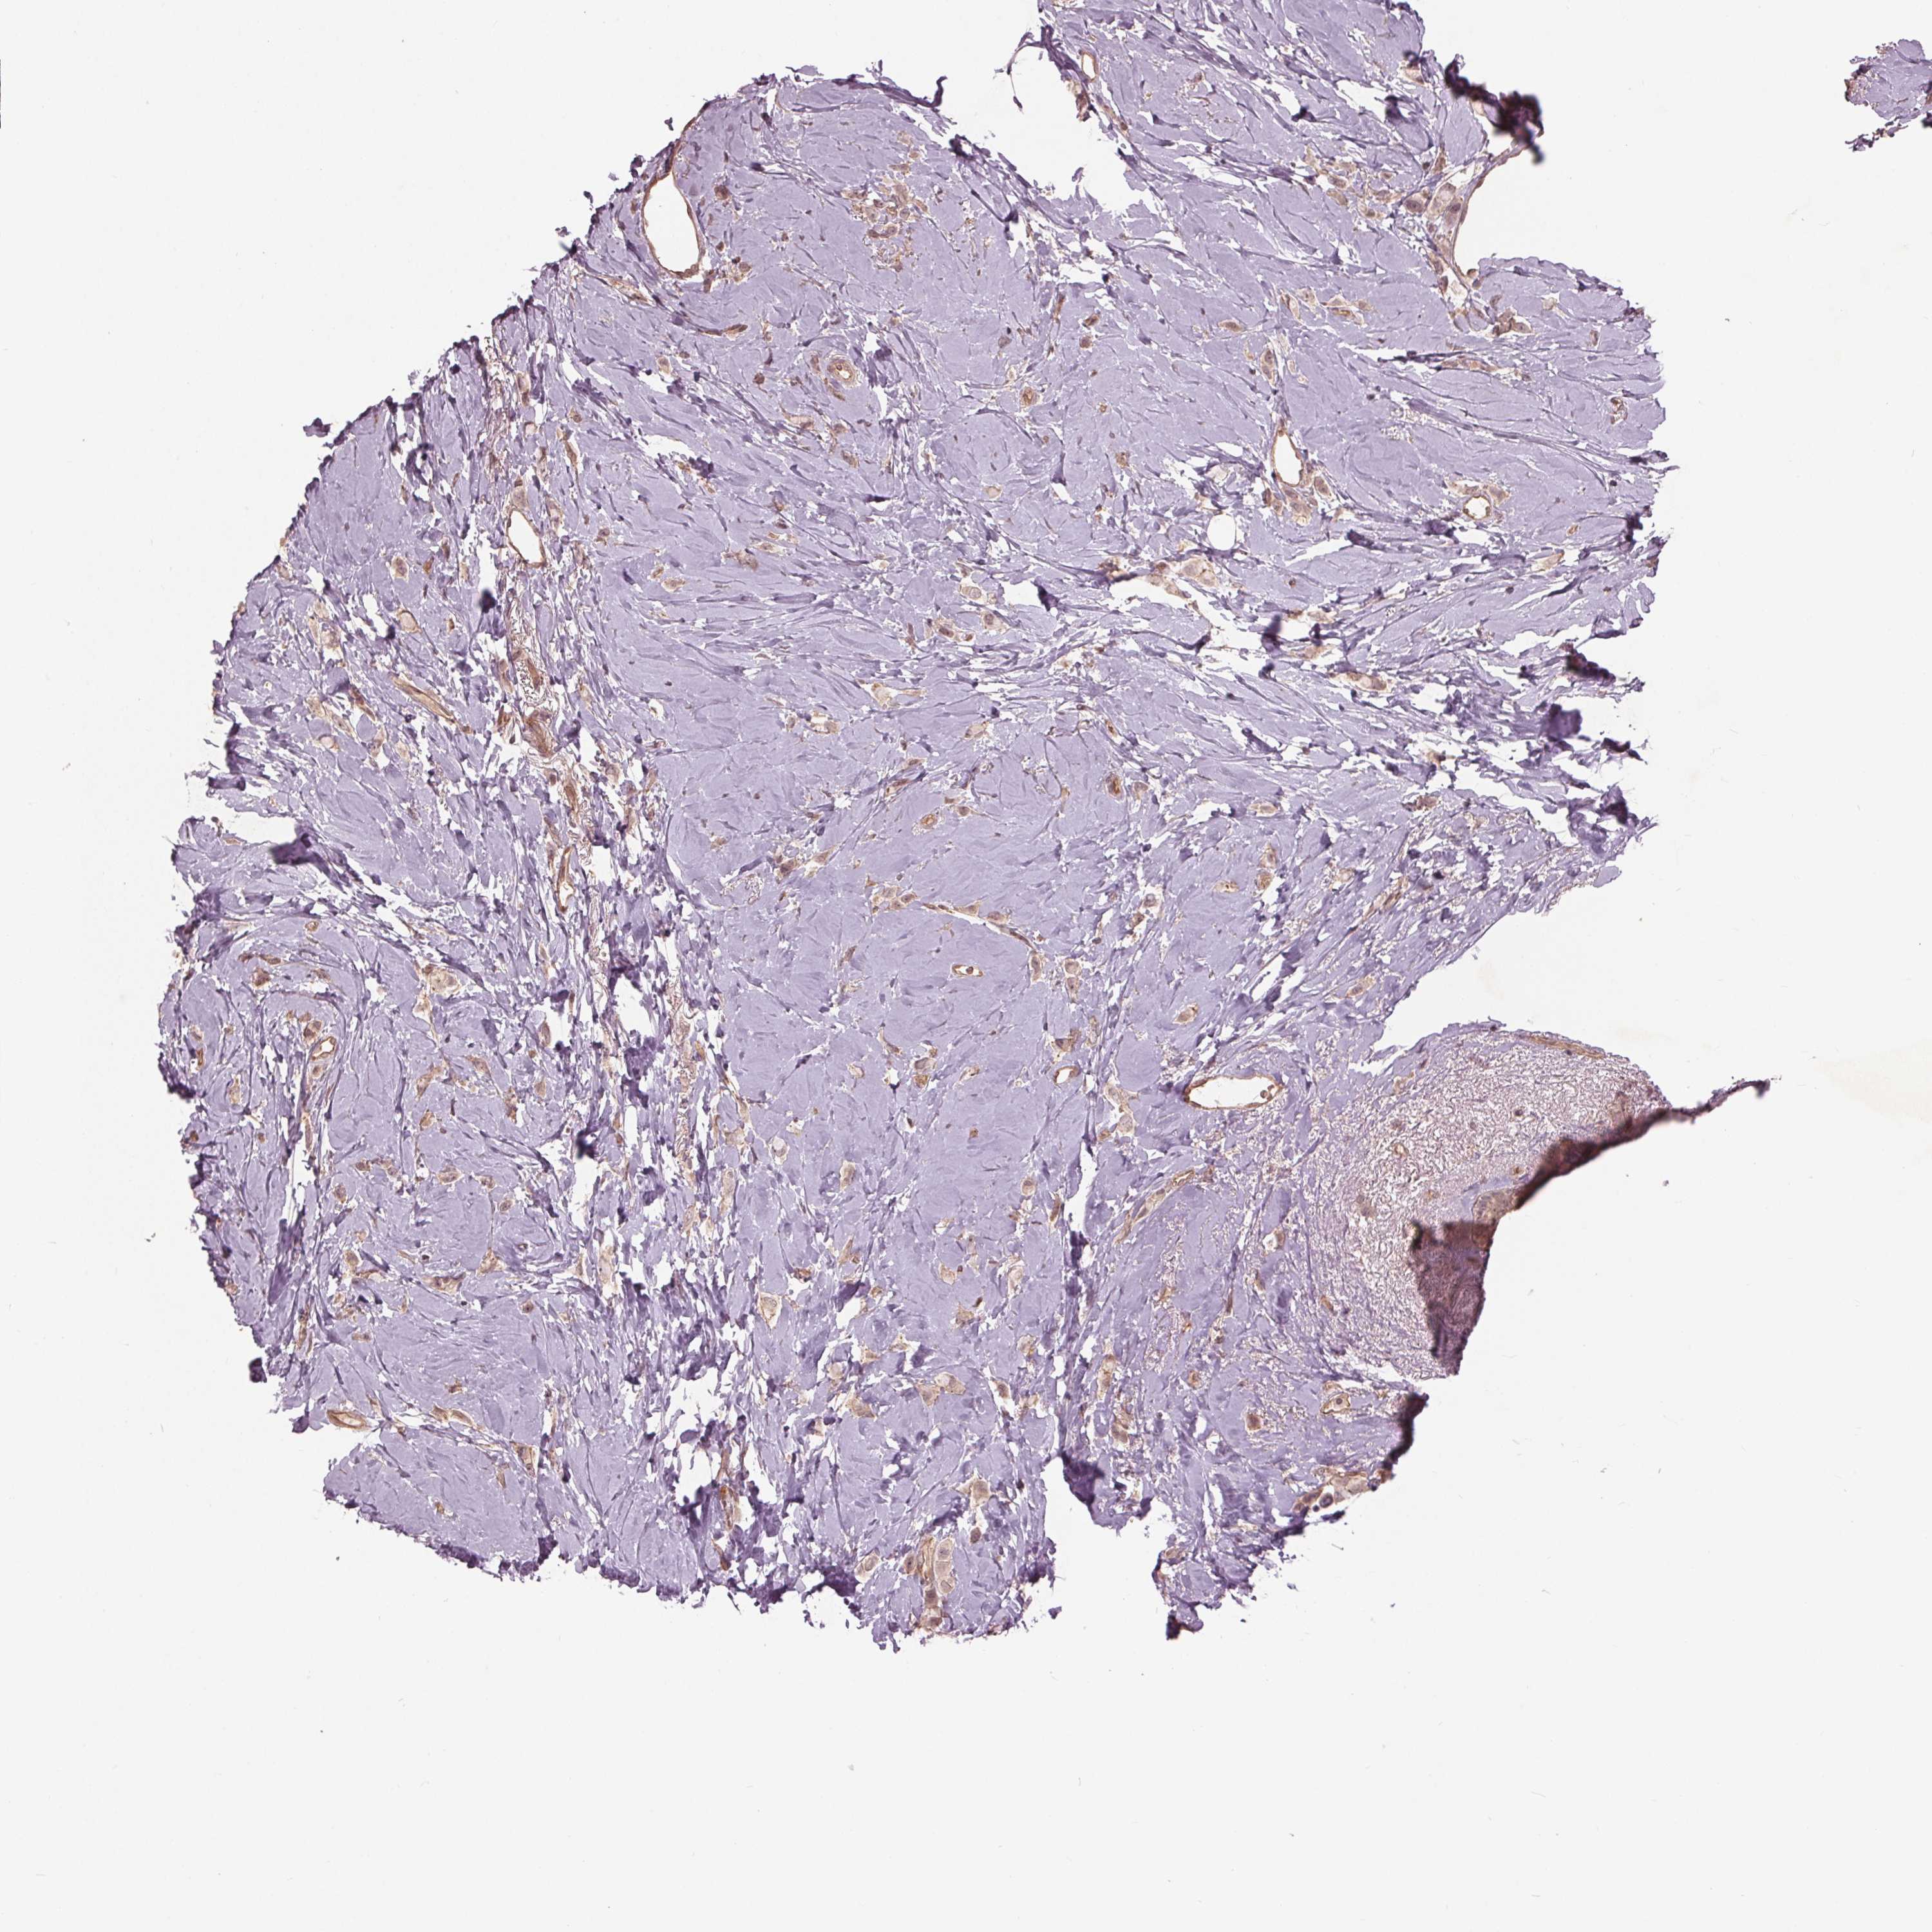

CANCER BREAST CANCER Show tissue menu

BRCA TCGA BRCA VALIDATION PROTEIN EXPRESSION

Breast cancer

Human cancer